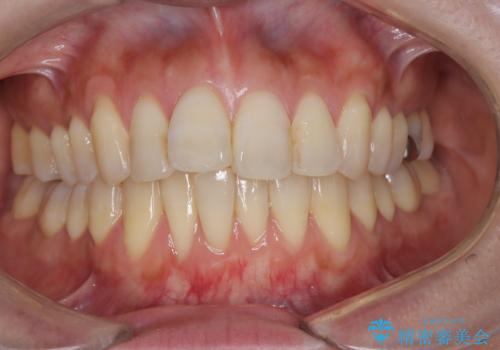

- 歯と歯の間に隙間があることを主訴に来院されました。

短期間での治療終了を希望され、ワイヤー矯正にて治療を行い1年ほどで治療を終了しております。

下顎前歯は矯正後補綴治療を行なっております。

期間や仕上がりで大変満足していただきました。